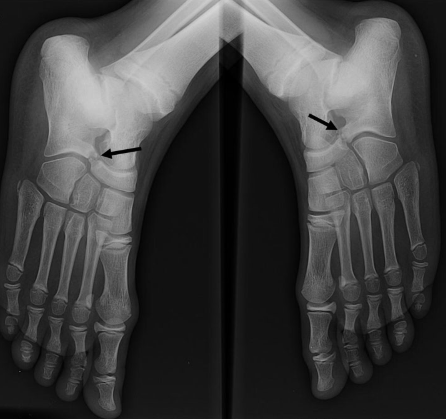

Coalitions tarsiennes

1. Synostose calcanéo-naviculaire